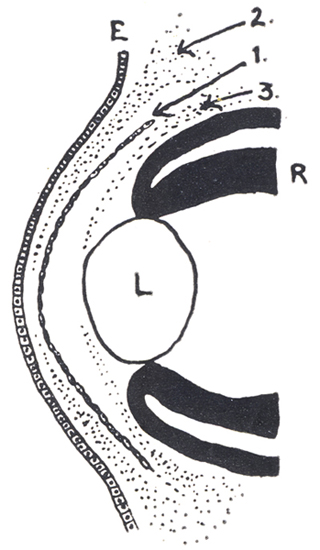

Síndrome de clivaje de la cámara anterior. Se puede explicar como debido a error en la diferenciación del tejido post-endotelial, que en el humano (12mm) ocupa la futura cámara anterior. Ese tejido debería normalmente formar la membrana pupilar y el estroma del Iris y debería perder totalmente sus conexiones con la capa mesoblastica que forma la membrana de Descemet.

Diagrama: El crecimiento de las 3 olas sucesivas de células “mesodérmicas asociadas”, con la diferenciación de la cámara anterior:

1era - Membrana de Descemet del Endotelio

2a - Sustancia propia de la córnea

3a - El Mesodermo del Iris y la membrana pupilar

E= Epitelio corneal. R= Retina. L=Cristalino